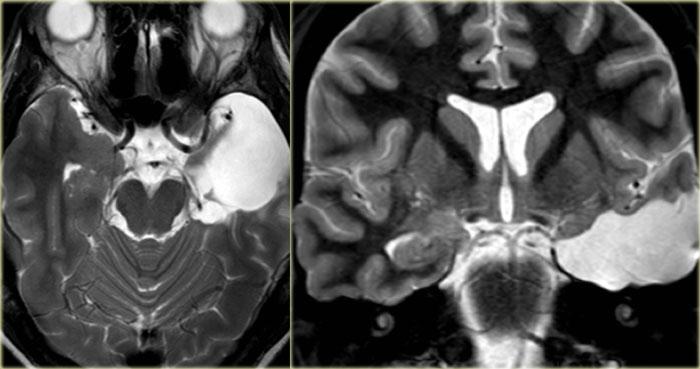

Hình ảnh T2W và FLAIR mặt phẳng coronal cho thấy xơ cứng thùy thái dương trong bên phải.

Lưu ý tình trạng mất thể tích, biểu hiện của teo não, gây giãn thứ phát sừng thái dương của não thất bên.

Tín hiệu cao trong hải mã phản ánh tình trạng gliosis.